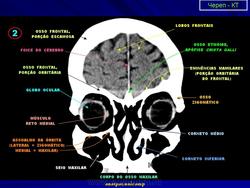

КТ головы в мягкотканном окне.

Нормальная КТ - анатомия головного мозга.